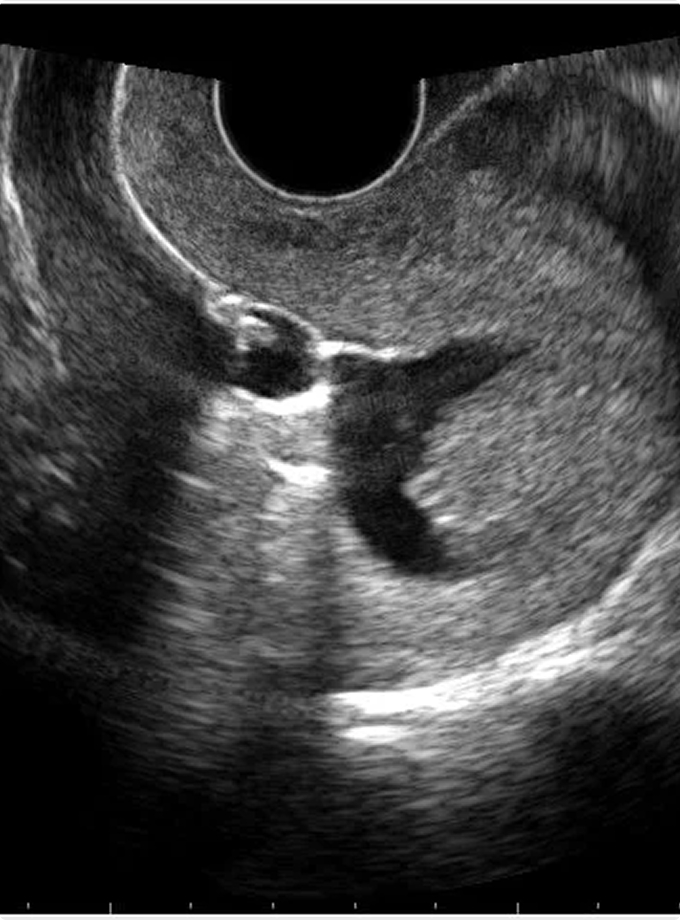

Your doctor has referred you to our clinic for a sonohysterogram. This ultrasound examination provides considerable information about your uterus and fallopian tubes, without the use of x-rays, x-ray dye, or an anesthetic.

The procedure itself takes 2-5 minutes. A thin catheter is placed through the cervix into the uterus. Normal saline (a salt water solution) is instilled through the catheter in order to allow us to see the inside of the uterus and check the fallopian tubes.